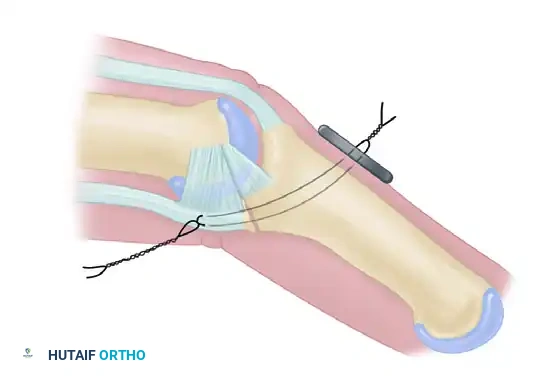

A size-matched segment of the distal hamate articular surface is carefully shaped to match the comminuted contour of the middle phalanx. The distal hamate (articulating with the base of the 4th and 5th metacarpals) possesses a central ridge that perfectly mimics the median ridge of the middle phalangeal base, providing exceptional coronal plane stability.

Figure 67-49C: Intraoperative fluoroscopic view of the distal hamate donor site.

Figure 67-49D: Fixation of the hemi-hamate graft with two minifragment screws to replicate the middle phalangeal base concavity.